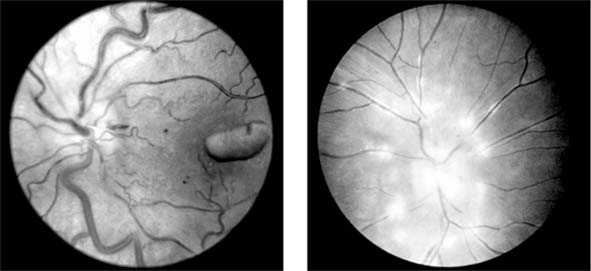

The ocular changes of leukemia occur primarily in those structures with a good blood supply, including the retina, the choroid, and the optic disk (Figure 15-14). Changes are most common in the acute leukemias, where hemorrhages are seen in the nerve fiber and preretinal layers.

Figure 15-14: Left: Retinal changes in chronic myeloid leukemia, where dilated veins and hemorrhages may be seen. Right: In acute lymphoblastic leukemia, infiltration of the disk may be seen.